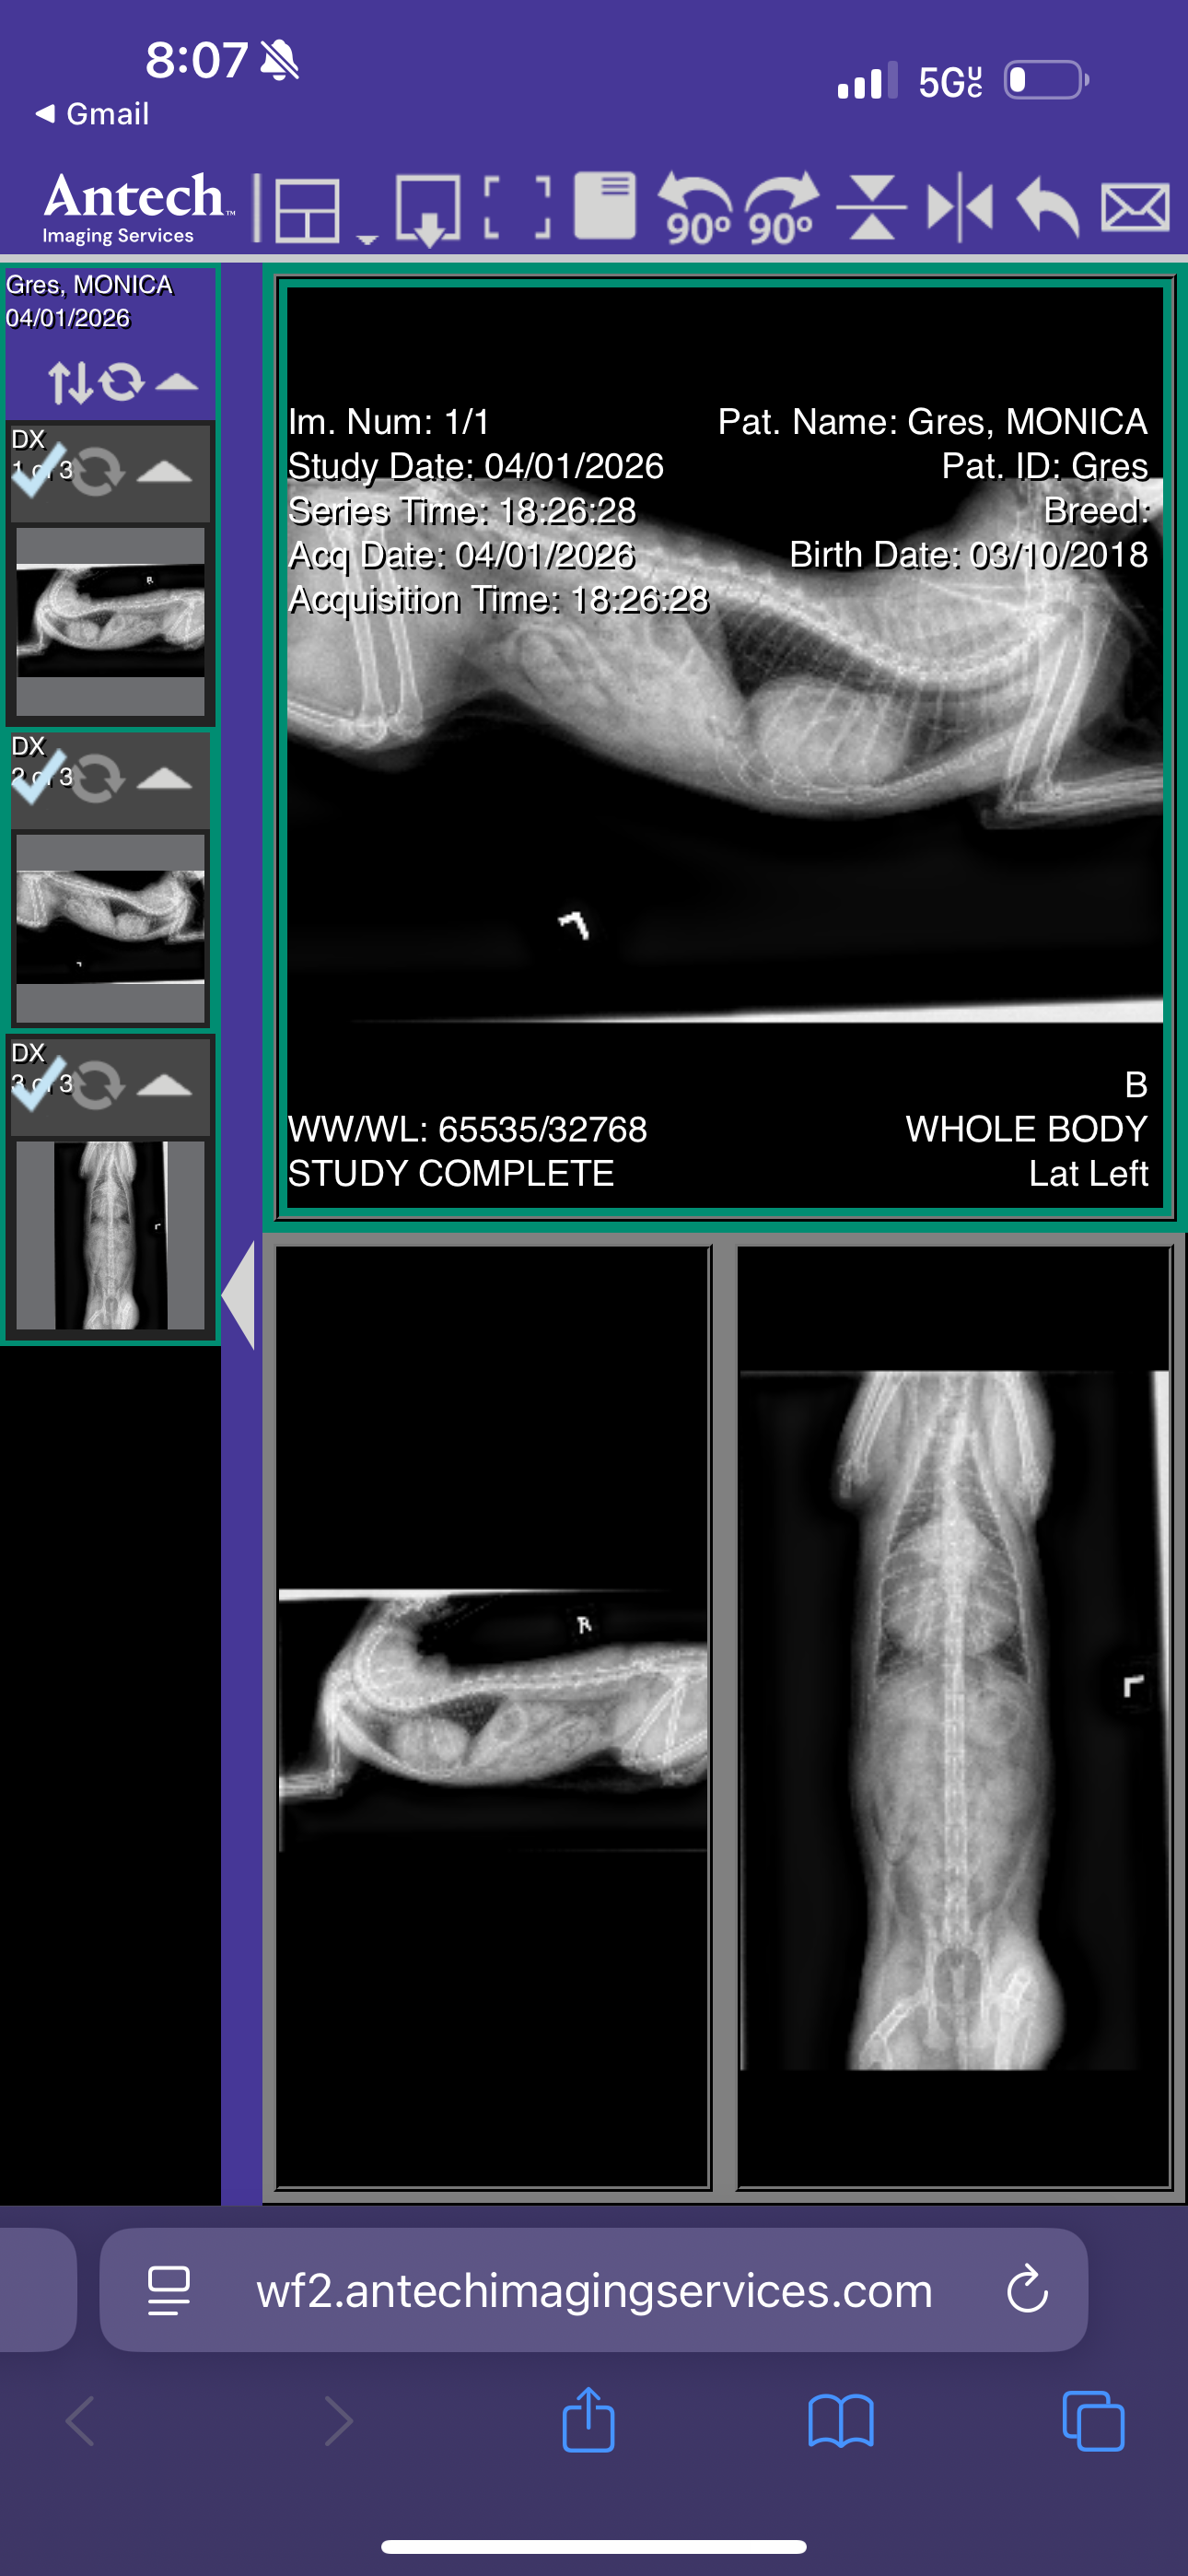

Monica is my 9-year-old cat and my precious sweet angel. She has been with me through the hardest periods of my life, offering comfort when I had no support at all. Now, Monica is facing a critical health crisis. She has a gigantic heart that is pressing on her tissue, a diaphragmic hernia next to it, and possible plastic obstruction in her stomach. Her left kidney is already deformed, causing her discomfort and putting her at high risk. Blood work shows she is intoxicated, and the doctor cannot give her steroids or other medications because of the risks to her heart. Without urgent medical help, her life expectancy is only about three months.